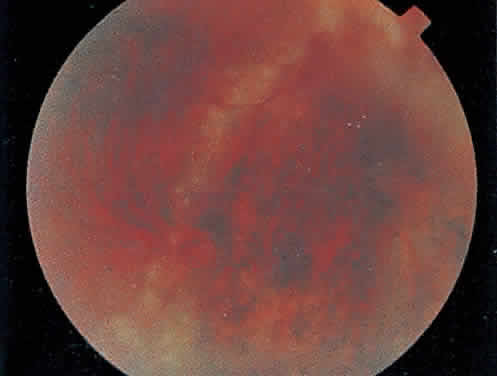

Over a course that usually spans weeks, infiltrates of CMV tend to assume two different patterns of clinical disease.11,12 The first pattern is called hemorrhagic and is characterized by broad geographic zones of retinal whitening. These large, geographic lesions are usually in close proximity to a major retinal blood vessel or the optic nerve. Satellite lesions are common. When the retinal necrosis associated with CMV retinitis becomes widespread, it is almost invariably associated with retinal hemorrhages. Although the border between necrotic and unaffected retina is sharply demarcated, the border itself appears irregular and jagged. Exudation into the retina or subretinal space may be seen, adding to the granular appearance of the retinitis. Juxtaposition of large zones of white, granular necrosis with those of red retinal hemorrhage has led this appearance of CMV retinitis to be described as either “pizza-pie” or “cheese and ketchup.” The retinal blood vessels, both arteries and veins, in the areas of necrosis commonly appear sheathed, secondary to a vasculitis. As a consequence, secondary retinal vascular occlusions, especially branch retinal vein obstructions, may occur in the course of CMV retinitis. Immune-mediated vascular damage may play a role in the vasculitis.12 Central healing of these lesions will occur as the infection progresses. Avasculitis resembling “frosted branch angiitis” hasbeen reported (Fig. 2).28 A second pattern of CMVretinitis has been labeled “granular” or “brushfireborder.” In this appearance, the focal granular infiltrates enlarge slowly across a line, leaving ever-increasing areas of destroyed retina and atrophic retinal pigment epithelium behind. Hemorrhages and vitreous cells are a less prominent feature. There appears to be direct cell-to-cell transfer of infected virions in this pattern of infection (Figs. 3 and 4). The brushfire border is commonly seen in CMV retinitis lesions anterior to the equator (Fig. 5). The significance, if any, of these two clinical patterns of CMV retinitis is not known, and, in some eyes, both patterns of disease can be seen simultaneously or in sequence. Progression of retinitis has been defined in clinical trials as movement of a lesion border at least 750 μm along a front that is 750 μm or more in length, development of a new CMV lesion in a previously involved eye or in the uninvolved fellow eye of a patient with baseline unilateral disease.29 Without treatment or improvement in the host's immune system, CMV retinitis is a relentless, slowly progressive infection resulting in blindness caused by total retinal necrosis, retinal detachment, or optic nerve involvement, in any combination.